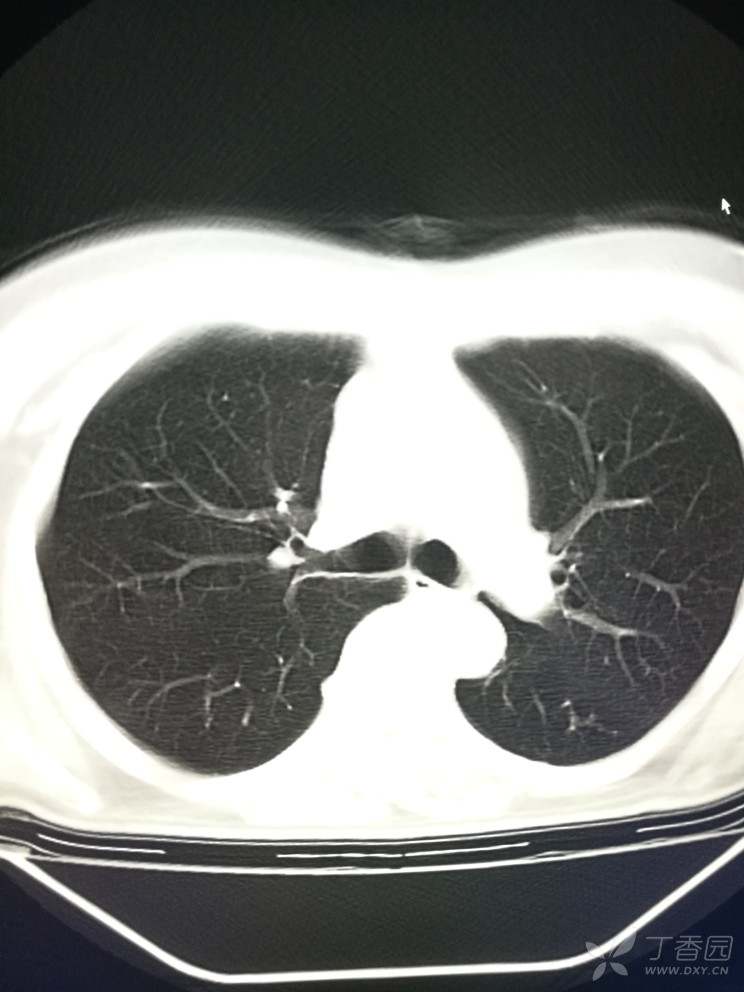

支气管炎ct影像学表现为双肺纹理增粗,增多,纹理紊乱,双肺斑点状